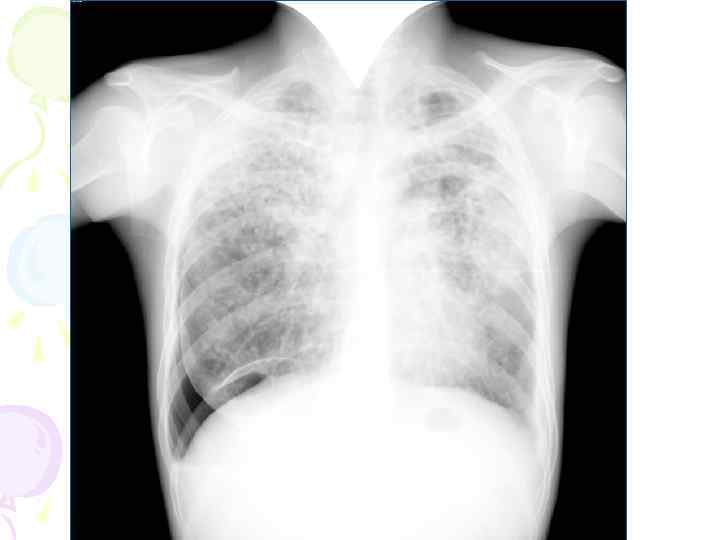

Рентгенологическая картина • множественные крупные / до 10 мм/ однотипные очаги преимущественно в верхних и средних отделах легких • Очаги округлой формы, малой и средней интенсивности, контуры нечеткие, часто расположены в виде цепочки вдоль продольных сосудов • Сливаясь, очаги образуют фокусы затемнения с участками просветления (распад) • При распаде в нескольких отдельных очагах формируются кольцевидные тени – штампованные каверны • При лимфогенной диссеминации очаговые тени с одной стороны, в средних и нижних отделах на фоне лимфангита, в корне кальцинаты